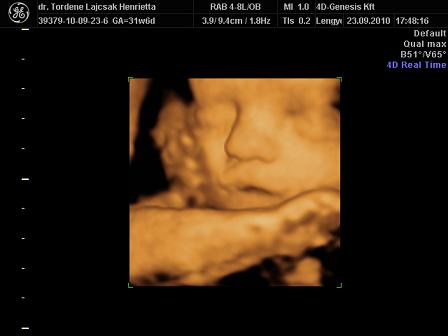

tegnap voltunk Uh-n. minden rendben van vele, egyre nagyobb. :)

méreteink:

BPD: 79,7 mm

HC: 292,5 mm

AC: 268,5 mm

FL: 57,8 mm (ezt nem tudta pontosan lemérni, mert érdekesen pózolt )

súly: 1700 g. (netes kalkulátor alapján 1750)

rakok róla néhány képet. :oops: és már 32 hetesek vagyunk...lassan finish.. :)